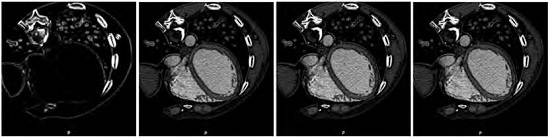

Figure 4 shows the results obtained after performing the experiment associated with the analysis of the similarity criterion components for S1 strategy. In this figure, we can observe a slice of a 3-D MSCT image in each case and for the configuration of the neighborhood space with n = 4. Each image is associated with each case (main, residual1, residual2 or full).

Meanwhile, when visually inspecting the results obtained from medical data, we observed that the components of our similarity-based image enhancement technique allow us to emphasize, to sharp, and to smooth medical image features, which facilitates the development of a solution to the problem of the medical image segmentation. The images of the first column of the Figure 5 show the utility of the component main to detect the edges of the anatomical structures located in a computed tomography slice of the thorax for both proposed strategies, S1 and S2. The remaining images of the Figure 5 show how the other components enhance the MSCT slice.

Comparing the values of the Tables 3-4, we observe that the score function, for both strategies S1 and S2, is higher if a neighborhood of n = 4 is considered when the component residual1 is used. In fact, the score function for S1 is better than score function for S2. Additionally, it can be seen that the minimal score in both S1 and S2 strategies is yielded for component main considering n = 4 as neighborhood size.

Reopening the issue of visual inspection, the local structures information (edges) of the original image is very well preserved in the processed image with minimal score function (images of first column of Figure 2, and first images on Figure 4-5). In fact, the component main of the criterion can be thought of as an edge detector operator. The score function associated to image processed with the component main in S2 strategy is significantly lower than the obtained with S1 strategy and the dispersión associated with this minimum average value is also low and it is 2.11%. This is because the main in S2 is linked to a IHPF generated using an edge detector.